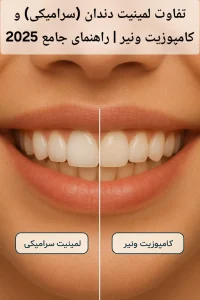

پس از پایان درمان ریشه، دندان با ترمیم های کامپوزیت یا انله های سرامیکی و یا روکش بازسازی میشود تا مقاومت و زیبایی آن بازگردد. در روشهای جدید از اسکن دیجیتال و طراحی CAD/CAM برای ساخت دقیقترین روکش استفاده میشود.

نرمافزارهای طراحی دیجیتال (CAD/CAM) برای ساخت دقیق روکشها، پستهای دندانی و ترمیمهای نهایی به کار میروند. این امر دقت و زیبایی درمان را افزایش میدهد.